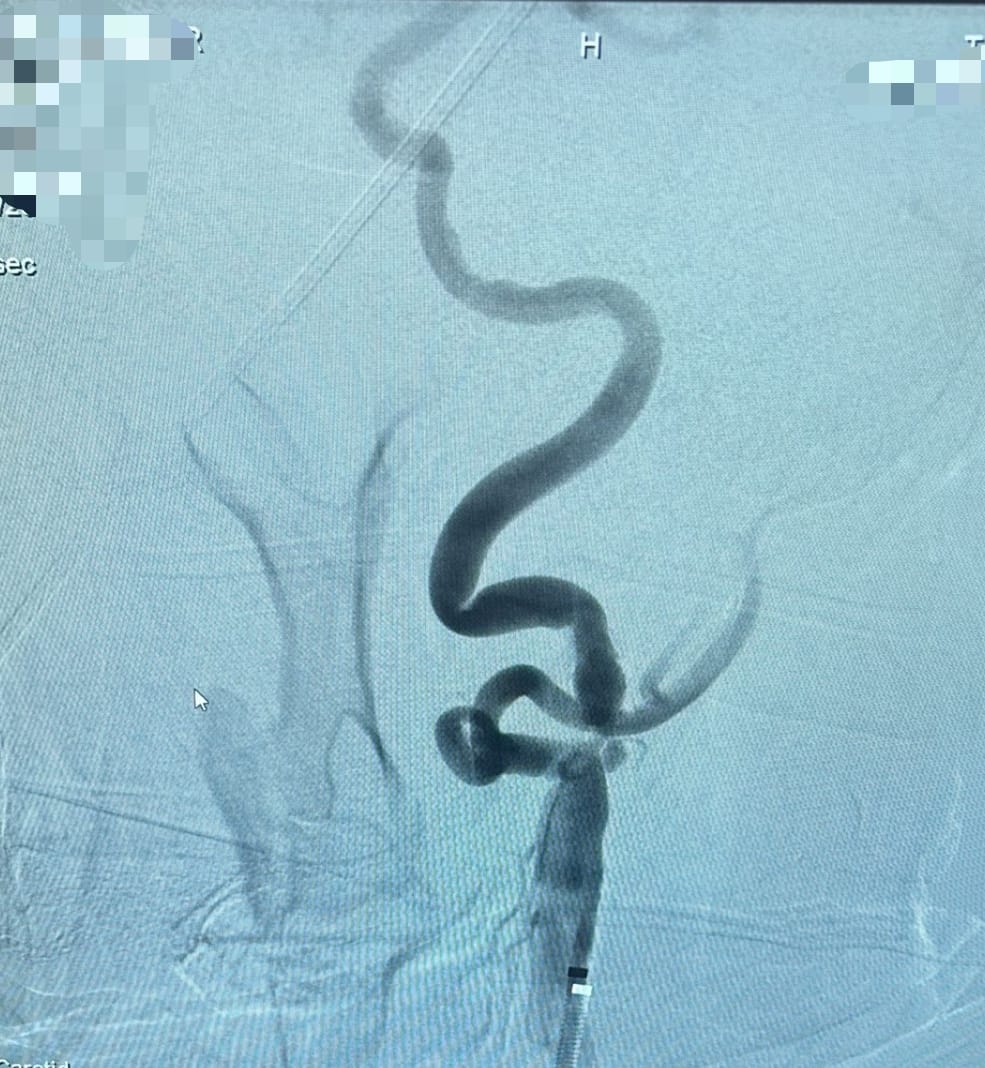

Şah damarında tespit edilen darlık, özel bir balonla genişletilir ve ardından stent adı verilen ince bir metal kafes yerleştirilerek damarın açık kalması sağlanır. Bu sayede kan akışı normale döner ve felç geçirme riski önemli ölçüde azalır. İşlem, ameliyat gerektirmeden anjiyografi ünitesinde yapılır.